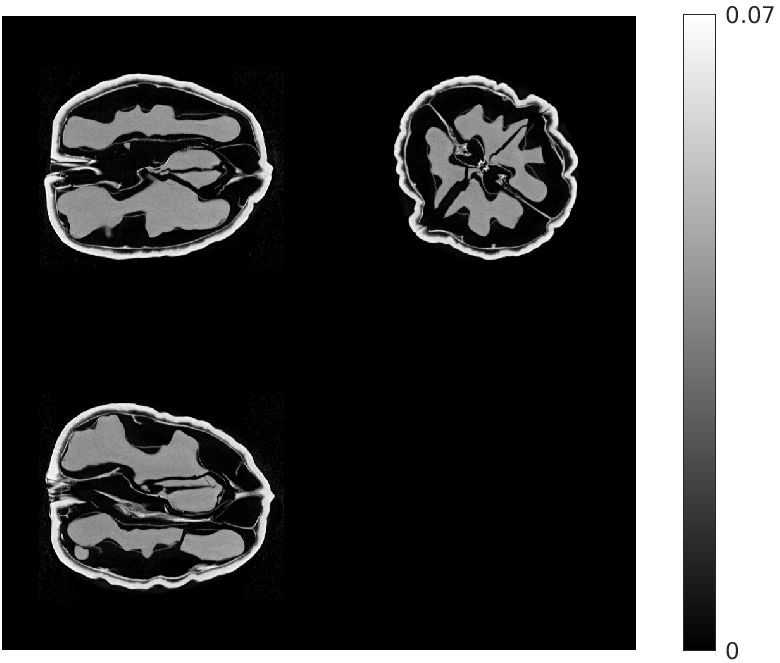

Fig. 2 gives an example reconstruction for 8 views (walnut 1 in Table I), showing central slices through the walnut in all three orientations (sagittal, coronal and transverse). The proposed algorithm provides significantly higher quality reconstructions than the other methods. This is particularly evident in the extent to which our algorithm is able to restore the finer features of the walnuts, and has fewer artifacts.

| Ground Truth Test Volume | Ground Truth Training Volume |

![]() |

| (a) (NMAE) | (b) (n/a) |

| FDK | EP Regularized Recon. |

| (c) (0.77) | (d) (0.45) |

| Destreaking CNN | Proposed |

| (e) (0.40) | (f) (0.26) |